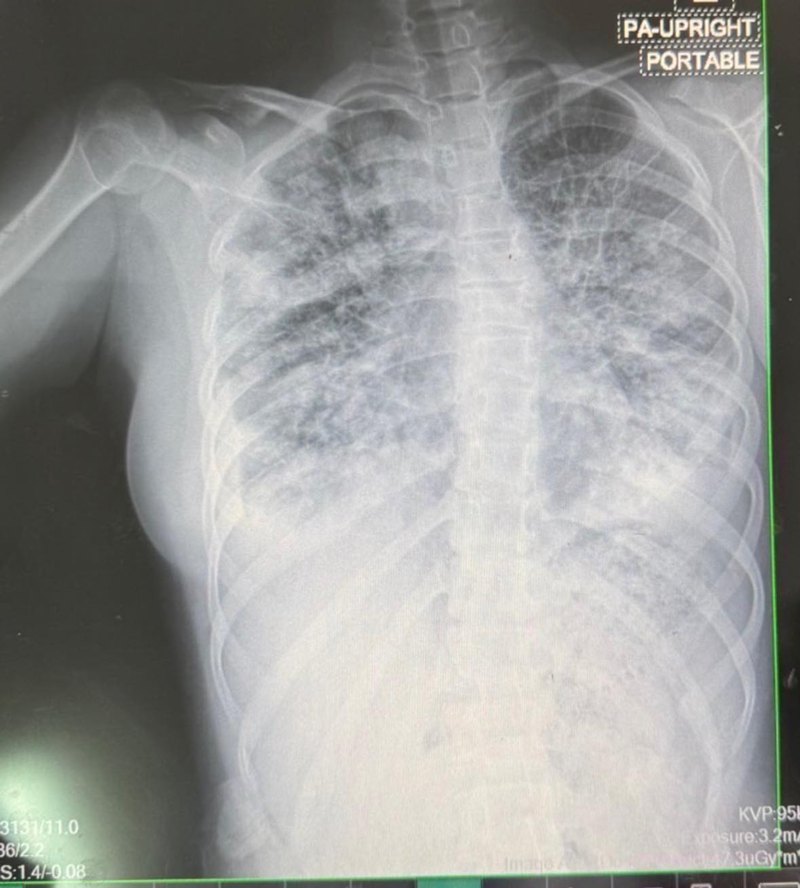

โดยระบุว่า "บุหรี่ไฟฟ้ามันร้ายจริง ๆ เด็กหญิง 14 ปี ใช้บุหรี่ไฟฟ้า 1 ปี เลิกใช้มา 2 เดือนเพราะร้านหยุดขาย มาด้วยเหนื่อย หายใจหอบ ซักประวัติกลับไปเริ่มสูบตอนอายุ 13 ปี ใช้เดือนละ 1 แท่ง สูบทุกวัน (9,000 สูบต่อเดือน) น้องบอกห้อยคอไปเลยอยากสูบตอนไหนก็ยกขึ้นมา EVALI เคสแรกเจอที่เลยค่ะ"

ภาพจาก เฟซบุ๊ก Sujitra Eaktasang

ด้านเพจ Drama-addict ให้ข้อมูลเพิ่มเติมว่า EVALI คือภาวะปอดอักเสบจากการสูบบุหรี่ไฟฟ้า เกิดจากสารเคมีต่าง ๆ ในน้ำยาบุหรี่ไฟฟ้า ไปทำให้เกิดการอักเสบที่ปอด จนปอดขาวปื้ดแบบในภาพ ซึ่งจะตามมาด้วยอาการเจ็บ แน่นหน้าอก เหนื่อยง่าย บางเคสไอเป็นเลือด ระบบหายใจล้มเหลว และเสียชีวิต